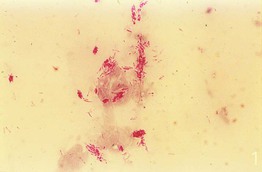

• When leprosy is suspected, a fold of skin is firmly squeezed and a small incision is made with a scalpel, with the liquid expressed smeared onto a slide, allowed to dry, and stained with a Fite or Ziehl–Neelsen stain (Fig. 2.13).

Fig. 2.13 Smear stained with a Ziehl–Neelsen stain demonstrating acid-fast bacilli in a patient with leprosy. From Peters W, Pasvol G. Tropical Medicine and Parasitology, 6th edn. London: Mosby, 2007.

• For bacilloscopy, the skin sites that are examined include the earlobes, forehead, chin, extensor forearms, dorsal fingers, buttocks, and trunk.

• While acid-fast Mycobacterium leprae organisms are found in ≤5% of patients with tuberculoid leprosy, they are seen in 100% of patients with lepromatous leprosy (see Chapter 62 on mycobacteria).